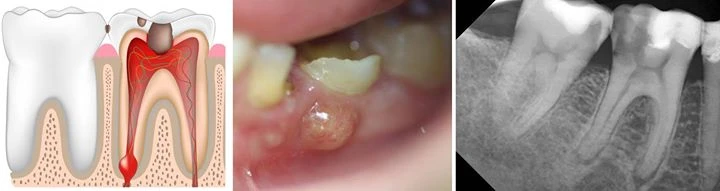

Đọc tiếpTrong nhiều năm qua, người ta đã cố gắng phát triển phân loại về bệnh lý tuỷ và mô quanh…

Đọc tiếpDo có nhiều kiểu gãy nứt chân răng khác nhau nên có vô số các biểu hiện và triệu chứng…